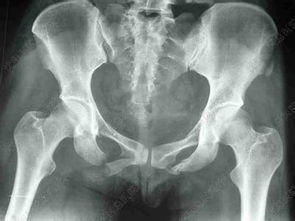

3脊柱骨折一般以壓縮性骨折居多,一般超過1/3最好就要做手術(shù),不然以后容易腰痛,這個(gè)是個(gè)人可以考慮利弊的,脊柱橫突和棘突的骨折一般無需特殊處理,壓迫脊髓的骨折都是需要手術(shù)治療的,藥物上我們一般給予甲潑尼龍沖擊治療,防止脊髓水腫不然隨著脊髓腫脹會造成截癱,粉碎性的骨折如果不是特別嚴(yán)重,并且沒有神經(jīng)系統(tǒng)癥狀是可以采取保守治療的,但是恢復(fù)的時(shí)間要比較長,股骨頭骨折和粗隆間骨折、股骨干骨折也是要采取切開手術(shù)固定,術(shù)前可以進(jìn)行牽引,方便術(shù)中復(fù)位。